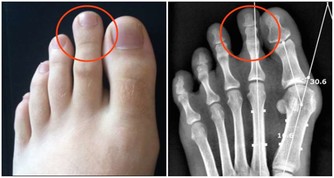

洗下來的牙結石很可能是這樣的,好大一塊。